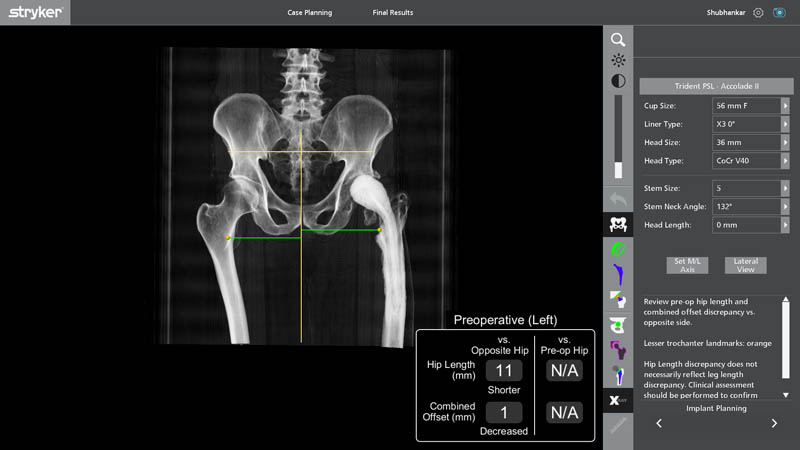

Preoperative Planning

- 3D Preoperative Planning with Segmentation

o Detailed separation (segmentation) of bone, old implant, and soft tissue - Accurate Assessment of Bone Loss